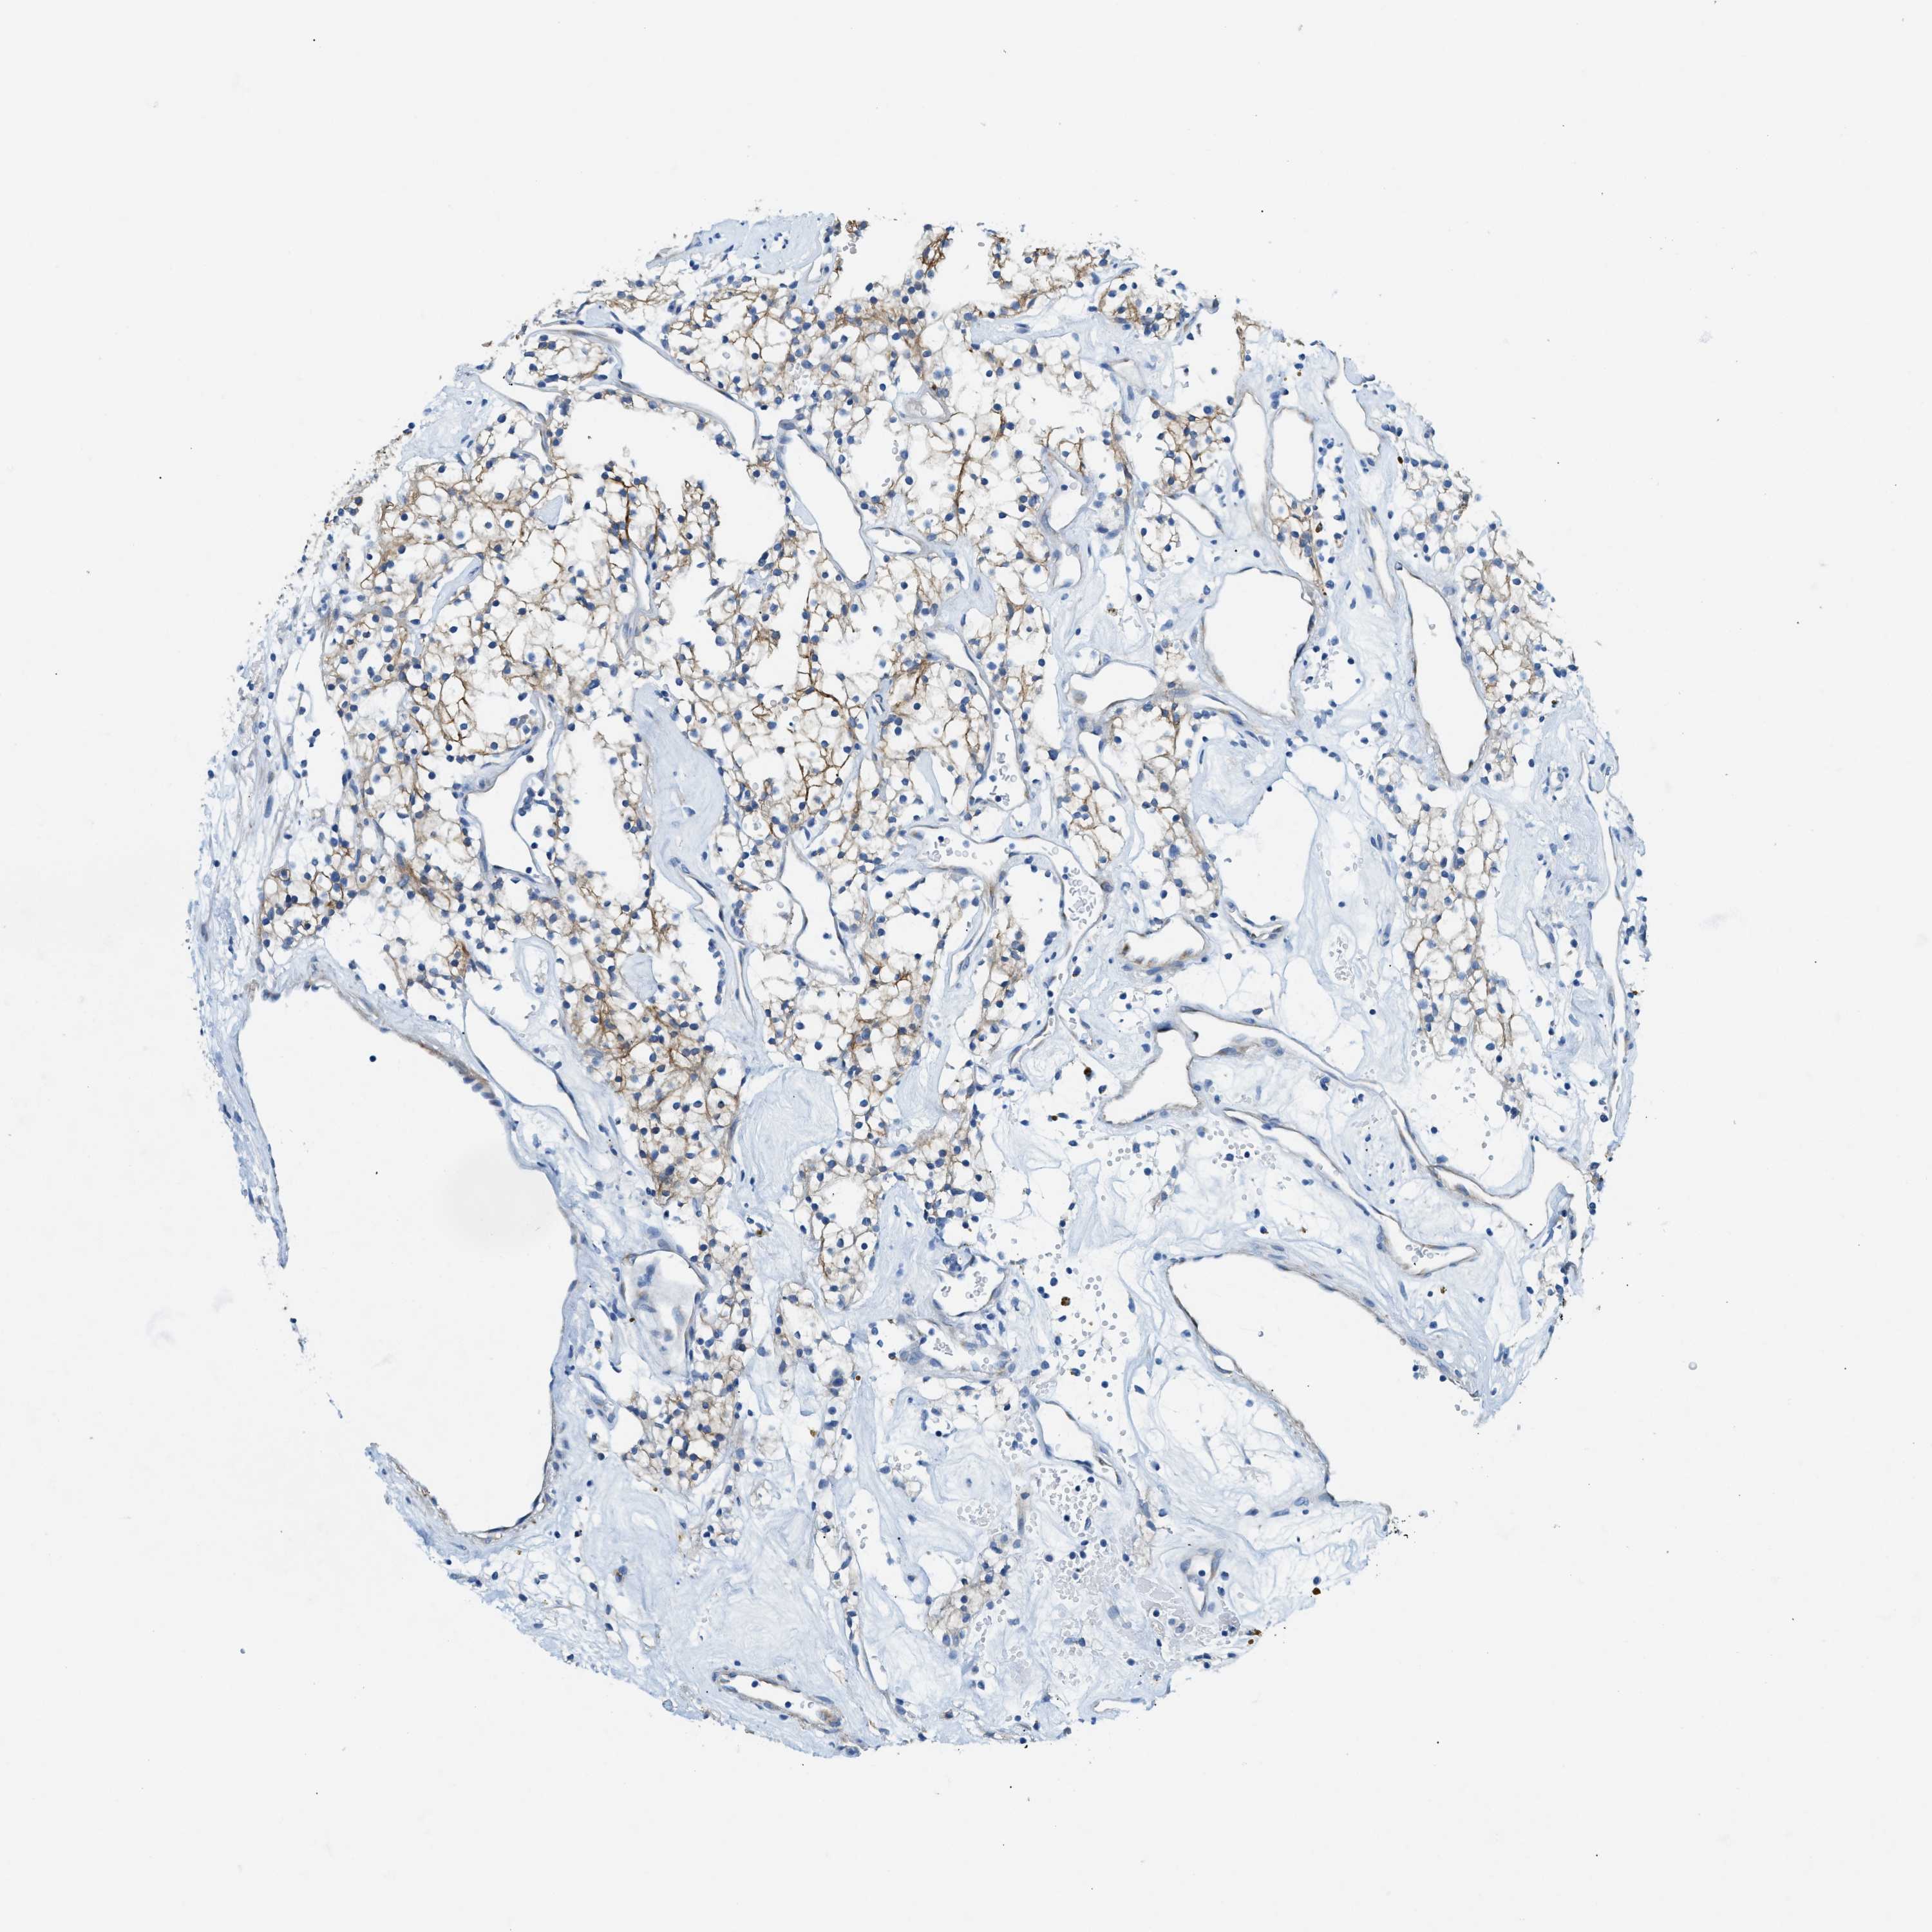

KIDNEY RENAL CLEAR CELL CARCINOMA (VALIDATION) - Interactive survival scatter ploti

The Survival Scatter plot shows the clinical status (i.e. dead or alive) for all individuals in the patient cohort, based on the same data that underlies the corresponding Kaplan-Meier plots. Patients that are alive at last time for follow-up are shown in blue and patients who have died during the study are shown in red.

The x-axis shows the expression levels (FPKM) of the investigated gene in the tumor tissue at the time of diagnosis. The y-axis shows the follow-up time after diagnosis (years). Both axes are complimented with kernel density curves demonstrating the data density over the axes. The top density plot shows the expression levels (FPKM) distribution among dead (red) and alive patients (blue). The right density plot shows the data density of the survived years of dead patients with high and low expression levels respectively, stratified using the cutoff indicated by the vertical dashed line through the Survival Scatter plot. This cutoff is automatically defined based on the FPKM cutoff that minimizes the p-score. The cutoff can be changed by dragging the vertical line or by entering a cutoff value in the square labeled "Current cut-off".

Under the Survival Scatter plot the p-score landscape (black curve; left axis) is shown together with dead median separation (red curve; right axis). Dead median separation is the difference in median mRNA expression between patients who have died with high and low expression, respectively. It is calculated as follows: median FPKM expression of dead patients with high expression - median FPKM expression of dead patients with low expression. This is intended to aid the user in visually exploring custom cutoffs and the associated p-scores and dead median separation.

Individual patient data is displayed and can be filtered by clicking on one or more of the category buttons on the top of the page. Categories describing expression level and patient information include: high, low, alive, dead, female, male and tumor stages. The scale of the x-axis can be toggled between linear and log-scale by clicking on the "x log" button. Mouse-over function shows TCGA ID, patient information and mRNA expression (FPKM) for each patient.

& Survival analysisi

Kaplan-Meier plots summarize results from analysis of correlation between mRNA expression level and patient survival. Patients were divided based on level of expression into one of the two groups "low" (under cut off) or "high" (over cut off). X-axis shows time for survival (years) and y-axis shows the probability of survival, where 1.0 corresponds to 100 percent.

ZDHHC13 is not prognostic in Kidney Renal Clear Cell Carcinoma (validation)

Best expression cut offi

: 11.34

Average pTPM 13.9

Number of samples 100